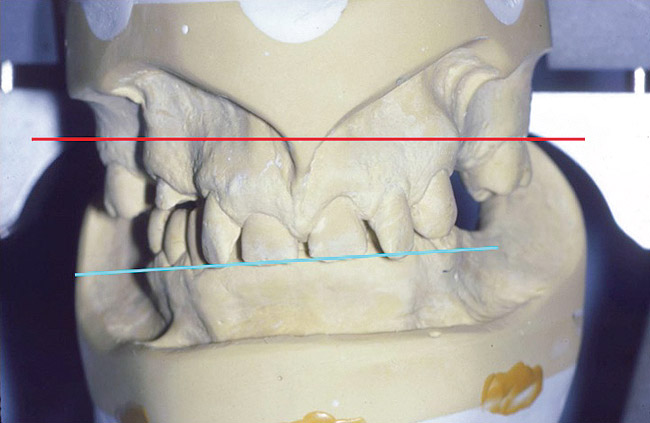

Figure 11. The anterior bar of the facebow is not parallel to the interpupillary line. This is not uncommon, as the interpupillary line often varies somewhat from the maxillary anterior plane of occlusion. A decision to alter an anterior plane would be made depending on the current esthetics and the incisional efficiency of the path of closure.

Figure 11